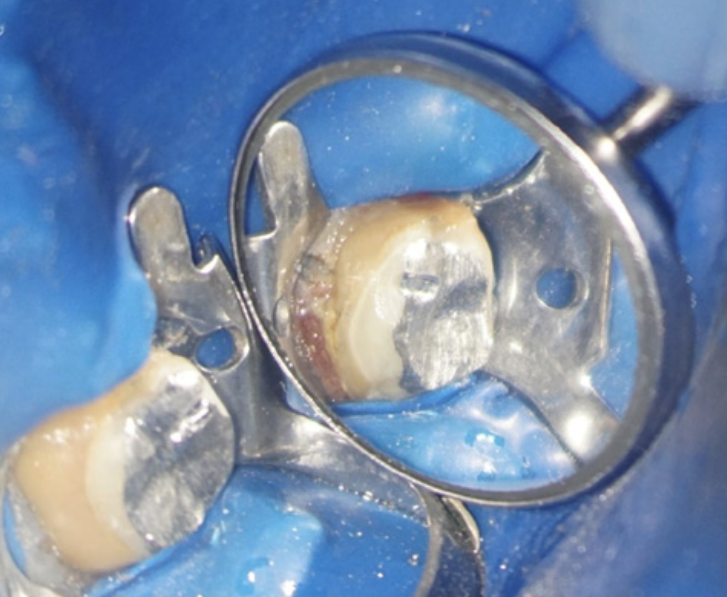

În acest caz, pacientul s-a prezentat după un abces acut în antecedente (durere puternică și spontană, cu caracter pulsatil) care a fost tratat cu antibiotice. La analiza imagisticii 3D remarcăm că există o comunicare între materialul din interiorul dintelui și spațiul dintre cele două rădăcini. Se mai evidențiază și material extrudat în acest spațiu, precum și pierdere osoasă. Deducem că este vorba de pierdere osoasă în furcație în urma cimentării unui pivot turnat. Acest pivot a fost cimentat într-un spațiu artificial creat în afara rădăcinii, această acțiune fiind un accident al tratamentului inițial (Fig. 4.12.4). Prima măsură este de a asigura izolarea cu diga dentară. Dintele prezintă o coroană artificială ce trebuie îndepărtată, diga ferește pacientul de contactul cu pulberile rezultate în urma tăierii coroanei (Fig. 4.12.5).

Pivotul de metal este voluminos și cimentat în două dintre canale și în perforație, așa că trebuie segmentat pentru a fi îndepărtat (Fig. 4.12.5, Fig. 4.12.6, Fig. 4.12.7).

După îndepărtarea unui segment din pivot, vedem cavitatea artificială care traversează grosimea dintelui, până în țesutul de susținere (Fig. 4.12.8). În țesutul de susținere se observă un material albastru, gumos. Este cel mai probabil un material din clasa silicaților, folosit pentru amprentarea spațiului din interiorul dintelui pentru confecționarea pivotului metalic (Fig. 4.12.9). Reușim să îndepărtăm o parte a acestui material și închidem perforația folosind un ciment bioceramic (MTA) (Fig.4.12.10, Fig. 4.12.11).